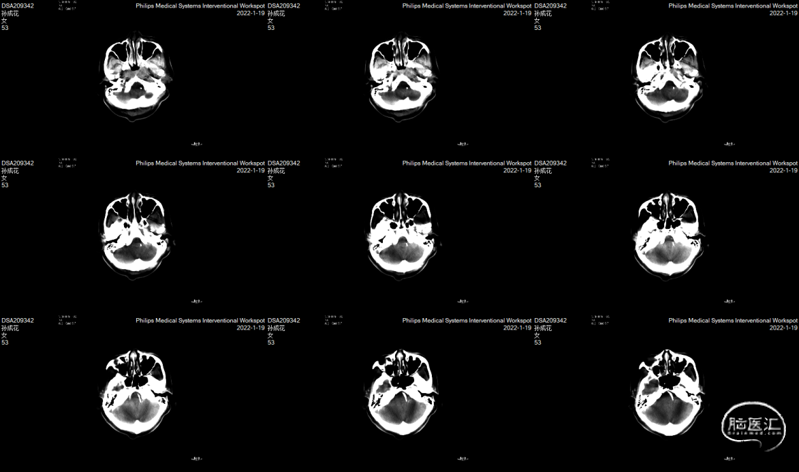

术中DynaCT。

术后4h CT。